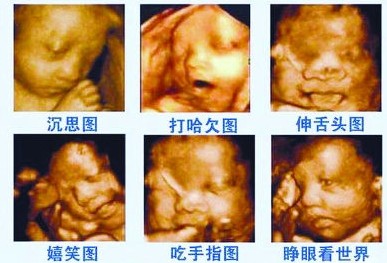

孕期的每一项产检,对于胎儿和准妈妈来说,都有着重要的意义。在众多产检中,被大家熟知并且较为关注的一项,是四维彩超。

很多人希望通过四维彩超可以提前看到宝宝的样子,以及在妈妈肚子里的“动态”情况。当然,更重要的是为了通过此项检查来确定胎儿的健康情况。

做四维彩超的最佳时间是孕24-28周,此时宝宝正是胎动比较活跃的时候,不配合检查的表现也是各异。

做四维彩超,除了可以有机会看到宝宝有趣的动态画面。有些准妈妈分享,做四维彩超时,跟医生沟通的一些“暗语”,还可以以此来猜测宝宝的性别。